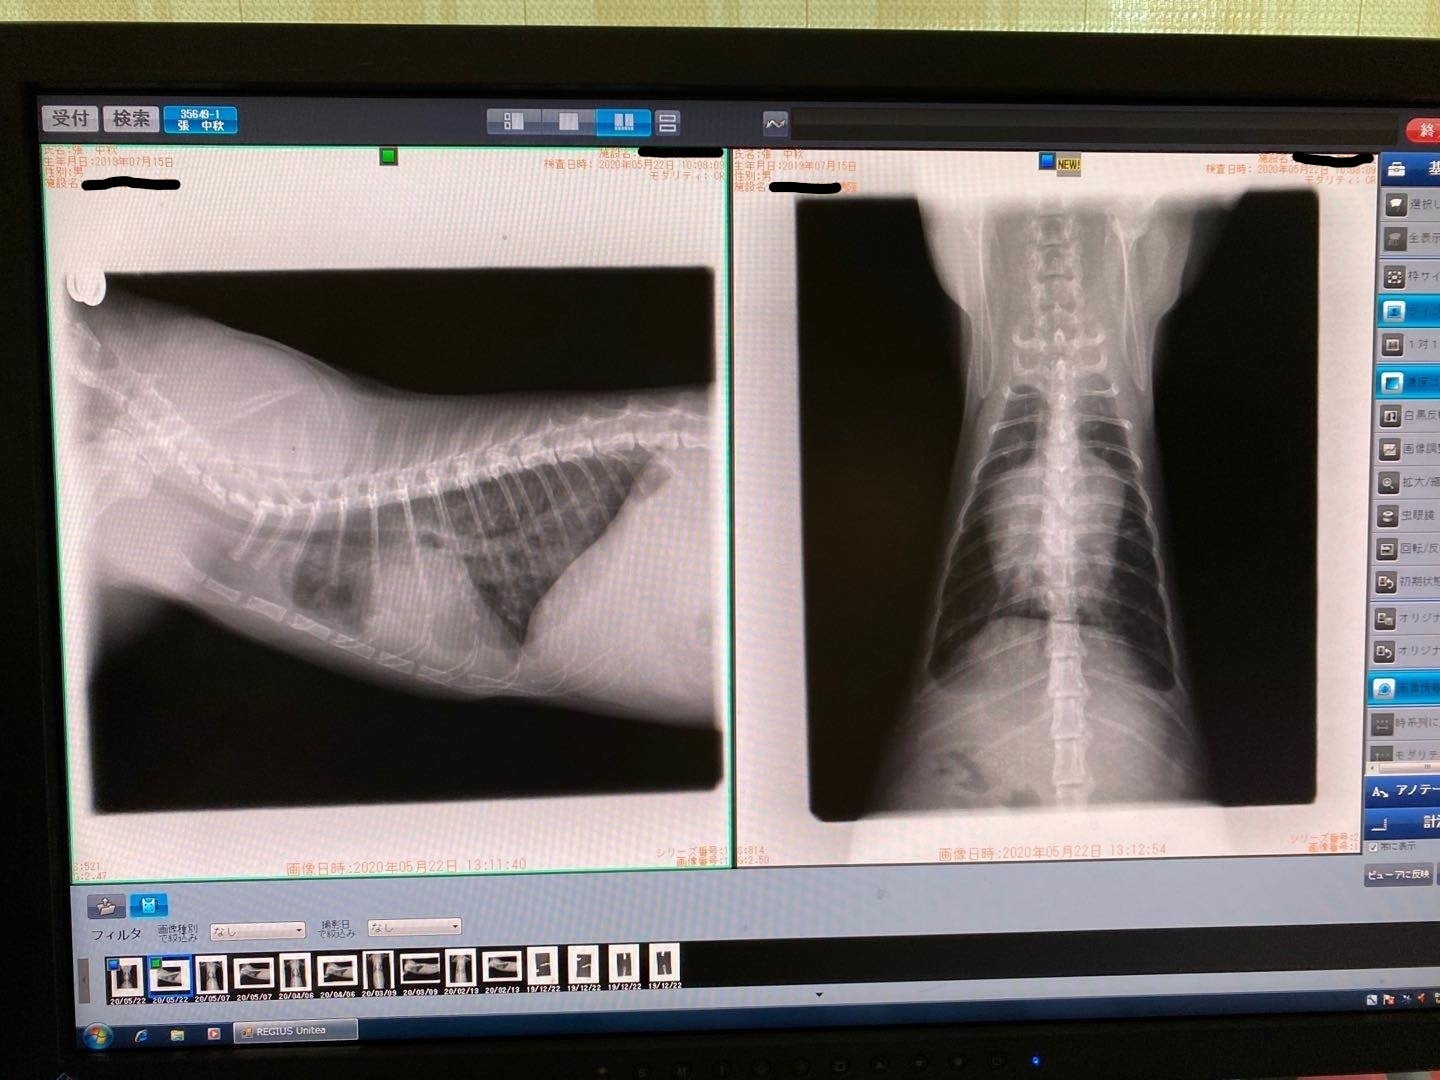

2/13去勢手術するため、身体検査をするとき、肺の中に薄い水影があって、念のため詳しい検査を行いました。

症状が軽い、判断が難しく、少し観察の時間が必要けど、最悪の場合はFIPを罹っているの可能性があると言われて、でも別の病気の可能性もあると言われました。3/9でレントゲン検査すると、水影が少し薄くになって、4月の検査も同じになって、FIPの可能性ではないかもと思います。けど、5月の検査はあまり変わらないになって、22日で急に発症になりました。前を振り返って見て、ずっと自分を責め続いている。